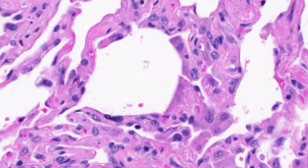

Figure 1 shows samples for 20 classes of Kimia Path960 dataset. In spite of the large texture variability, one can spot some inter-class similarities which may affect the classification. Figure 2 illustrates the large intra-class variability which is another challenging aspect of this dataset.